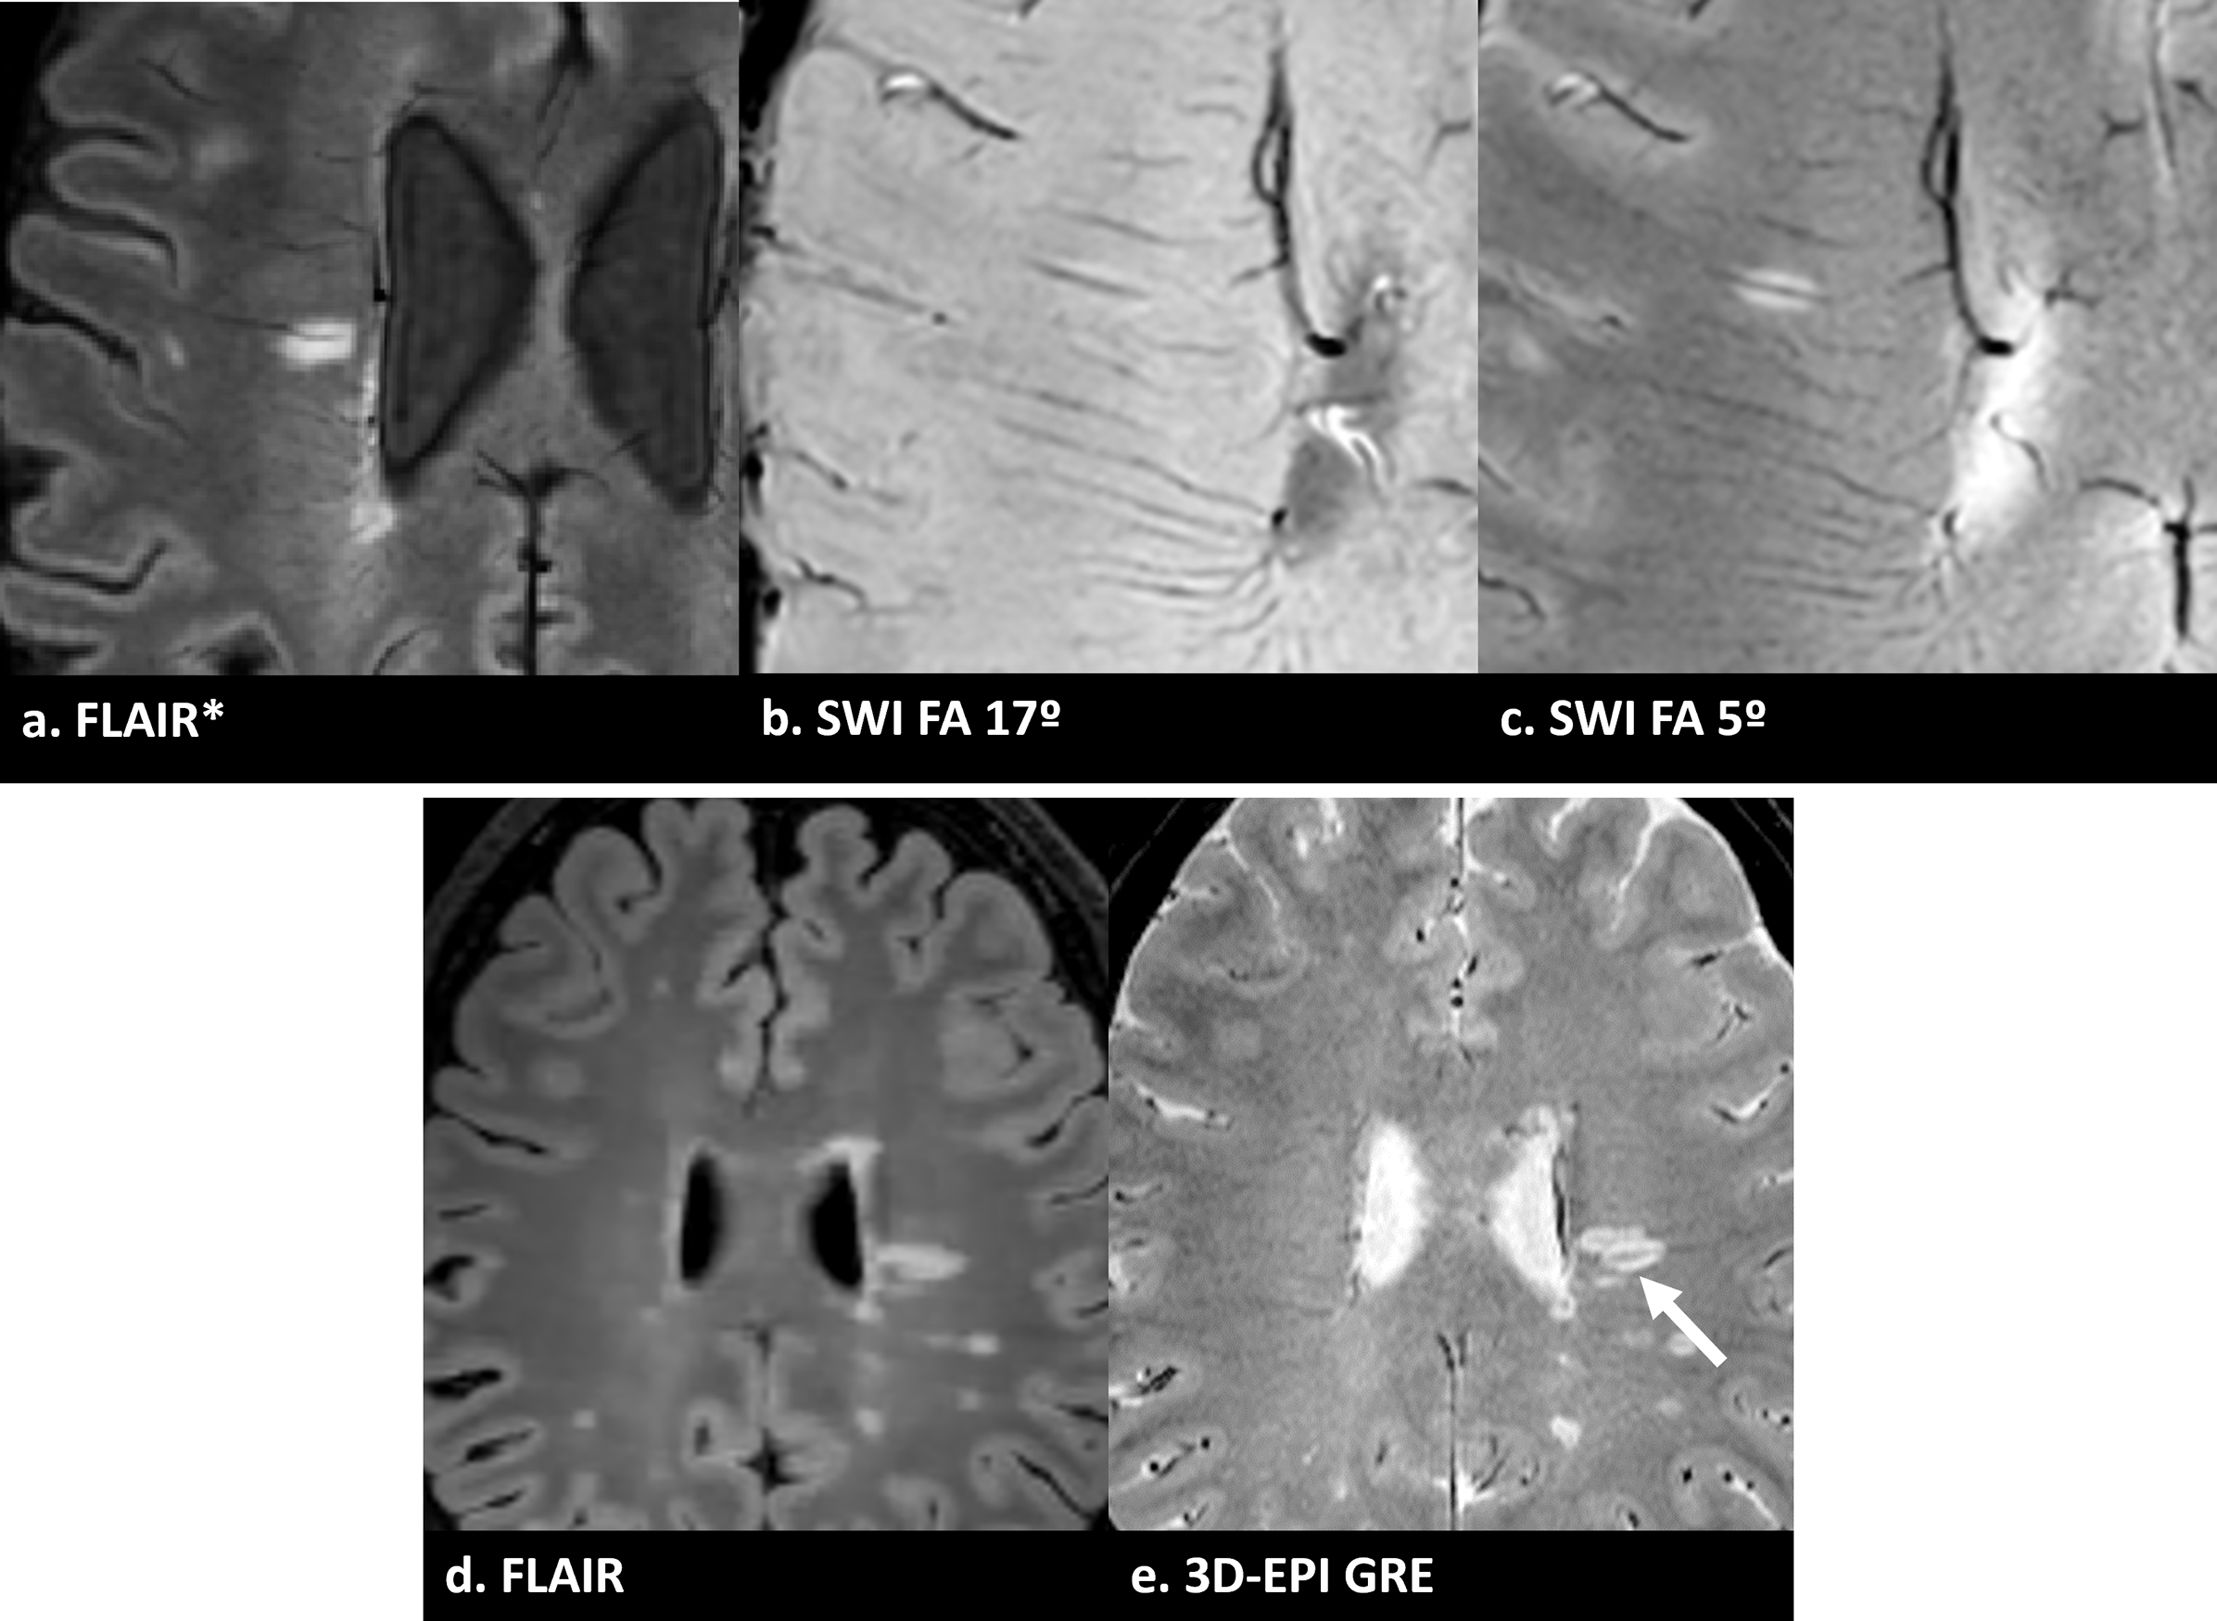

(a) Imagen FLAIR* que muestra una lesión de sustancia blanca con un signo de la vena central claramente visible (flecha). (b) SWI procesada estándar (flip angle 17°): la lesión aparece sutilmente hipointensa debido a la potenciación T1, dificultando su distinción de la sustancia blanca circundante y oscureciendo la identificación del CVS. (c) SWI procesada optimizada (flip angle 5°): la misma lesión ahora aparece hiperintensa debido al aumento de la potenciación T2*, con la vena central claramente visible. Esto ilustra por qué se recomienda la optimización del flip angle bajo o la fusión FLAIR* para una evaluación fiable del CVS. (d) otra imagen FLAIR de un paciente diferente, y (e) imágenes 3D-EPI GRE alineadas del mismo paciente que muestran claramente el CVS (flecha).

Consideraciones prácticas. La secuencia óptima para la visualización de CVS es la imagen ecoplanar de eco gradiente 3D (3D-EPI GRE). Con algunos proveedores, esta secuencia se adquiere de forma segmentada, lo que reduce el tiempo de adquisición. Además, en algunos sistemas, también permite la reconstrucción de imágenes de fase, lo que permite la detección simultánea de PRL. SWI La imagen por susceptibilidad magnética (SWI por sus siglas en inglés) es una alternativa a las imágenes 3D-EPI, sin embargo, puede requerir una optimización adecuada de secuencias. Las secuencias SWI estándar pueden tener una ponderación T1 excesiva que hace que las lesiones sean iso- o hipointensas, ocultando la vena central; Se recomienda un flip angle más bajo (aproximadamente 5°)8. FLAIR*,FLAIR (fluid attenuated inversion recovery) generado mediante la multiplicación voxel de imágenes FLAIR registradas y 3D-EPI, representa un enfoque óptimo ya que muestra simultáneamente lesiones hiperintensas y venas hipointensas26. La administración de gadolinio durante o inmediatamente antes de la adquisición sensible a la susceptibilidad mejora la detección de CVS, especialmente a 1,5T8. Además, dependiendo de las características de ponderación, la SWI poscontraste demuestra un efecto de «brillo en T1» que puede mejorar la detección de lesiones captantes de gadolinio en comparación con la imagen estándar potenciada solo en T127. La prevalencia del CVS varía según la ubicación, siendo más alta en lesiones periventriculares (hasta un 94%) y de sustancia blanca profunda, con datos limitados para otras regiones6. El impacto de la optimización de secuencias en la detección de CVS se ilustra en la figura 2.

Imagen optimizada SWI: TR ∼30ms, TE ∼20ms, con un flip angle bajo (∼5°) para asegurar un contraste adecuado entre lesión y fondo. Esto es fundamental: las secuencias estándar de SWI que usan flip angles por defecto (∼15°) hacen que las lesiones sean iso- o hipointensas, haciendo que la detección de CVS sea subóptima. Si solo existe la SWI estándar, se recomienda la fusión o la combinación aritmética con T2-FLAIR para una evaluación precisa de la CVS8.